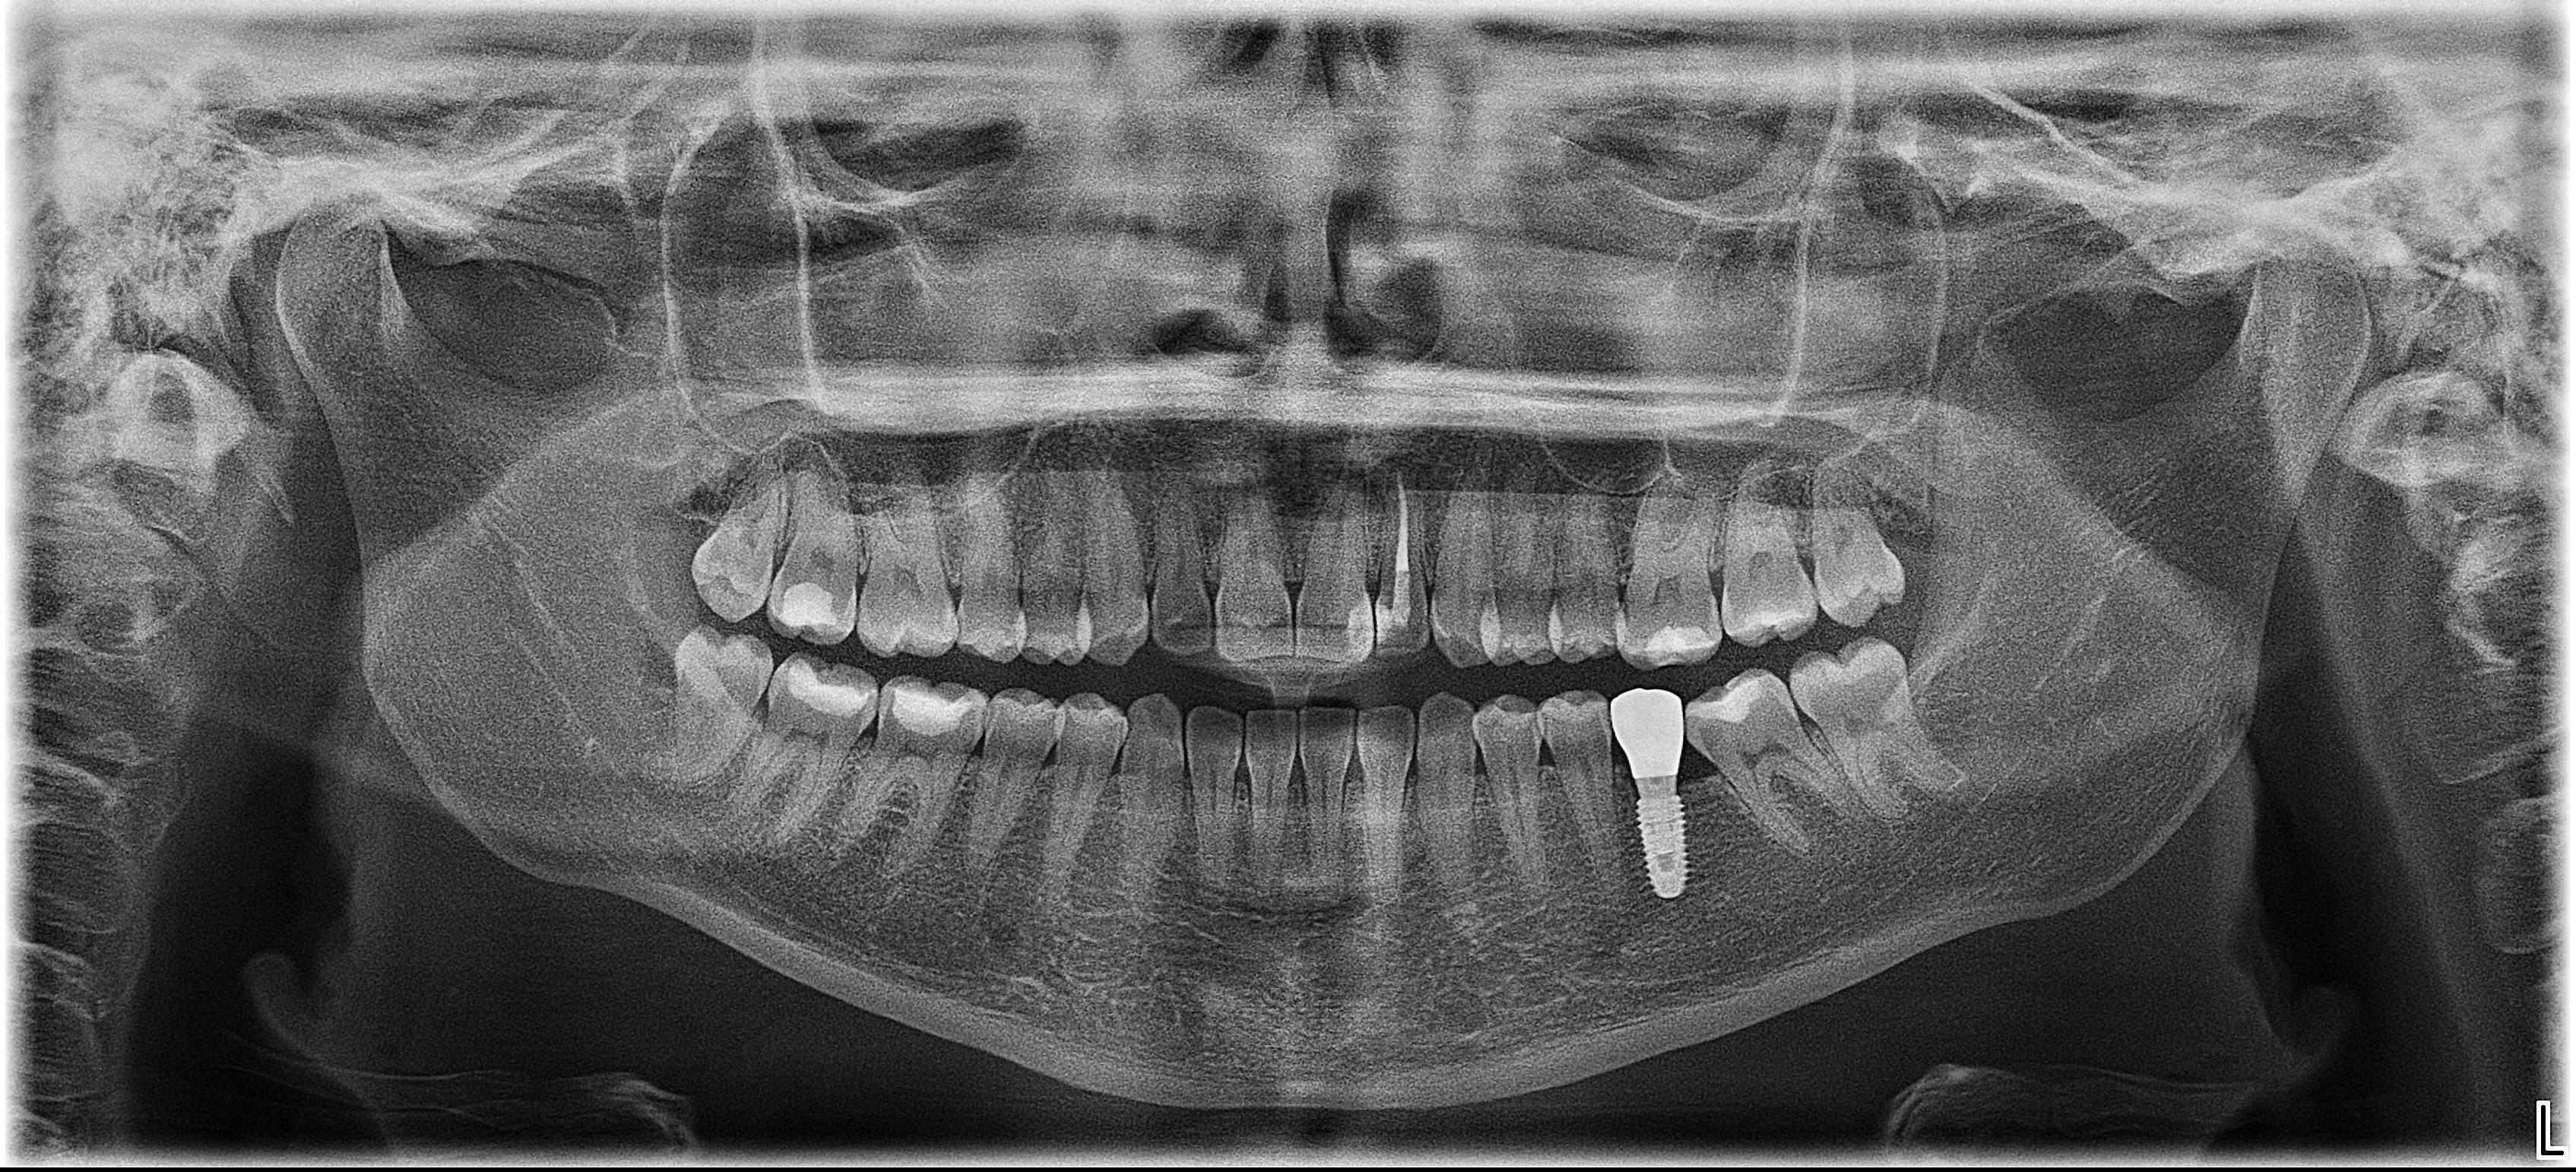

Sistemul Dantură pe implanturi dentare implică un număr redus, dar totuși extrem de eficient de implanturi dentare, care inserate în poziții cheie conferă siguranța de care ai nevoie / siguranța unei danturi sănătoase. Mai mult decât atât, această intervenție este minim invazivă, iar recuperarea este mult mai ușoară.